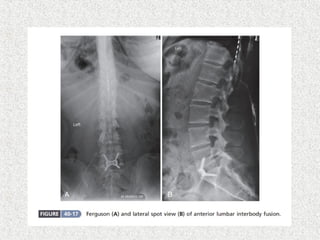

 Ant lumbar interbody fusion with post supplemental

fixation

 Used if small transverse process

 Salvage procedure if non union in posterolateral

fusion